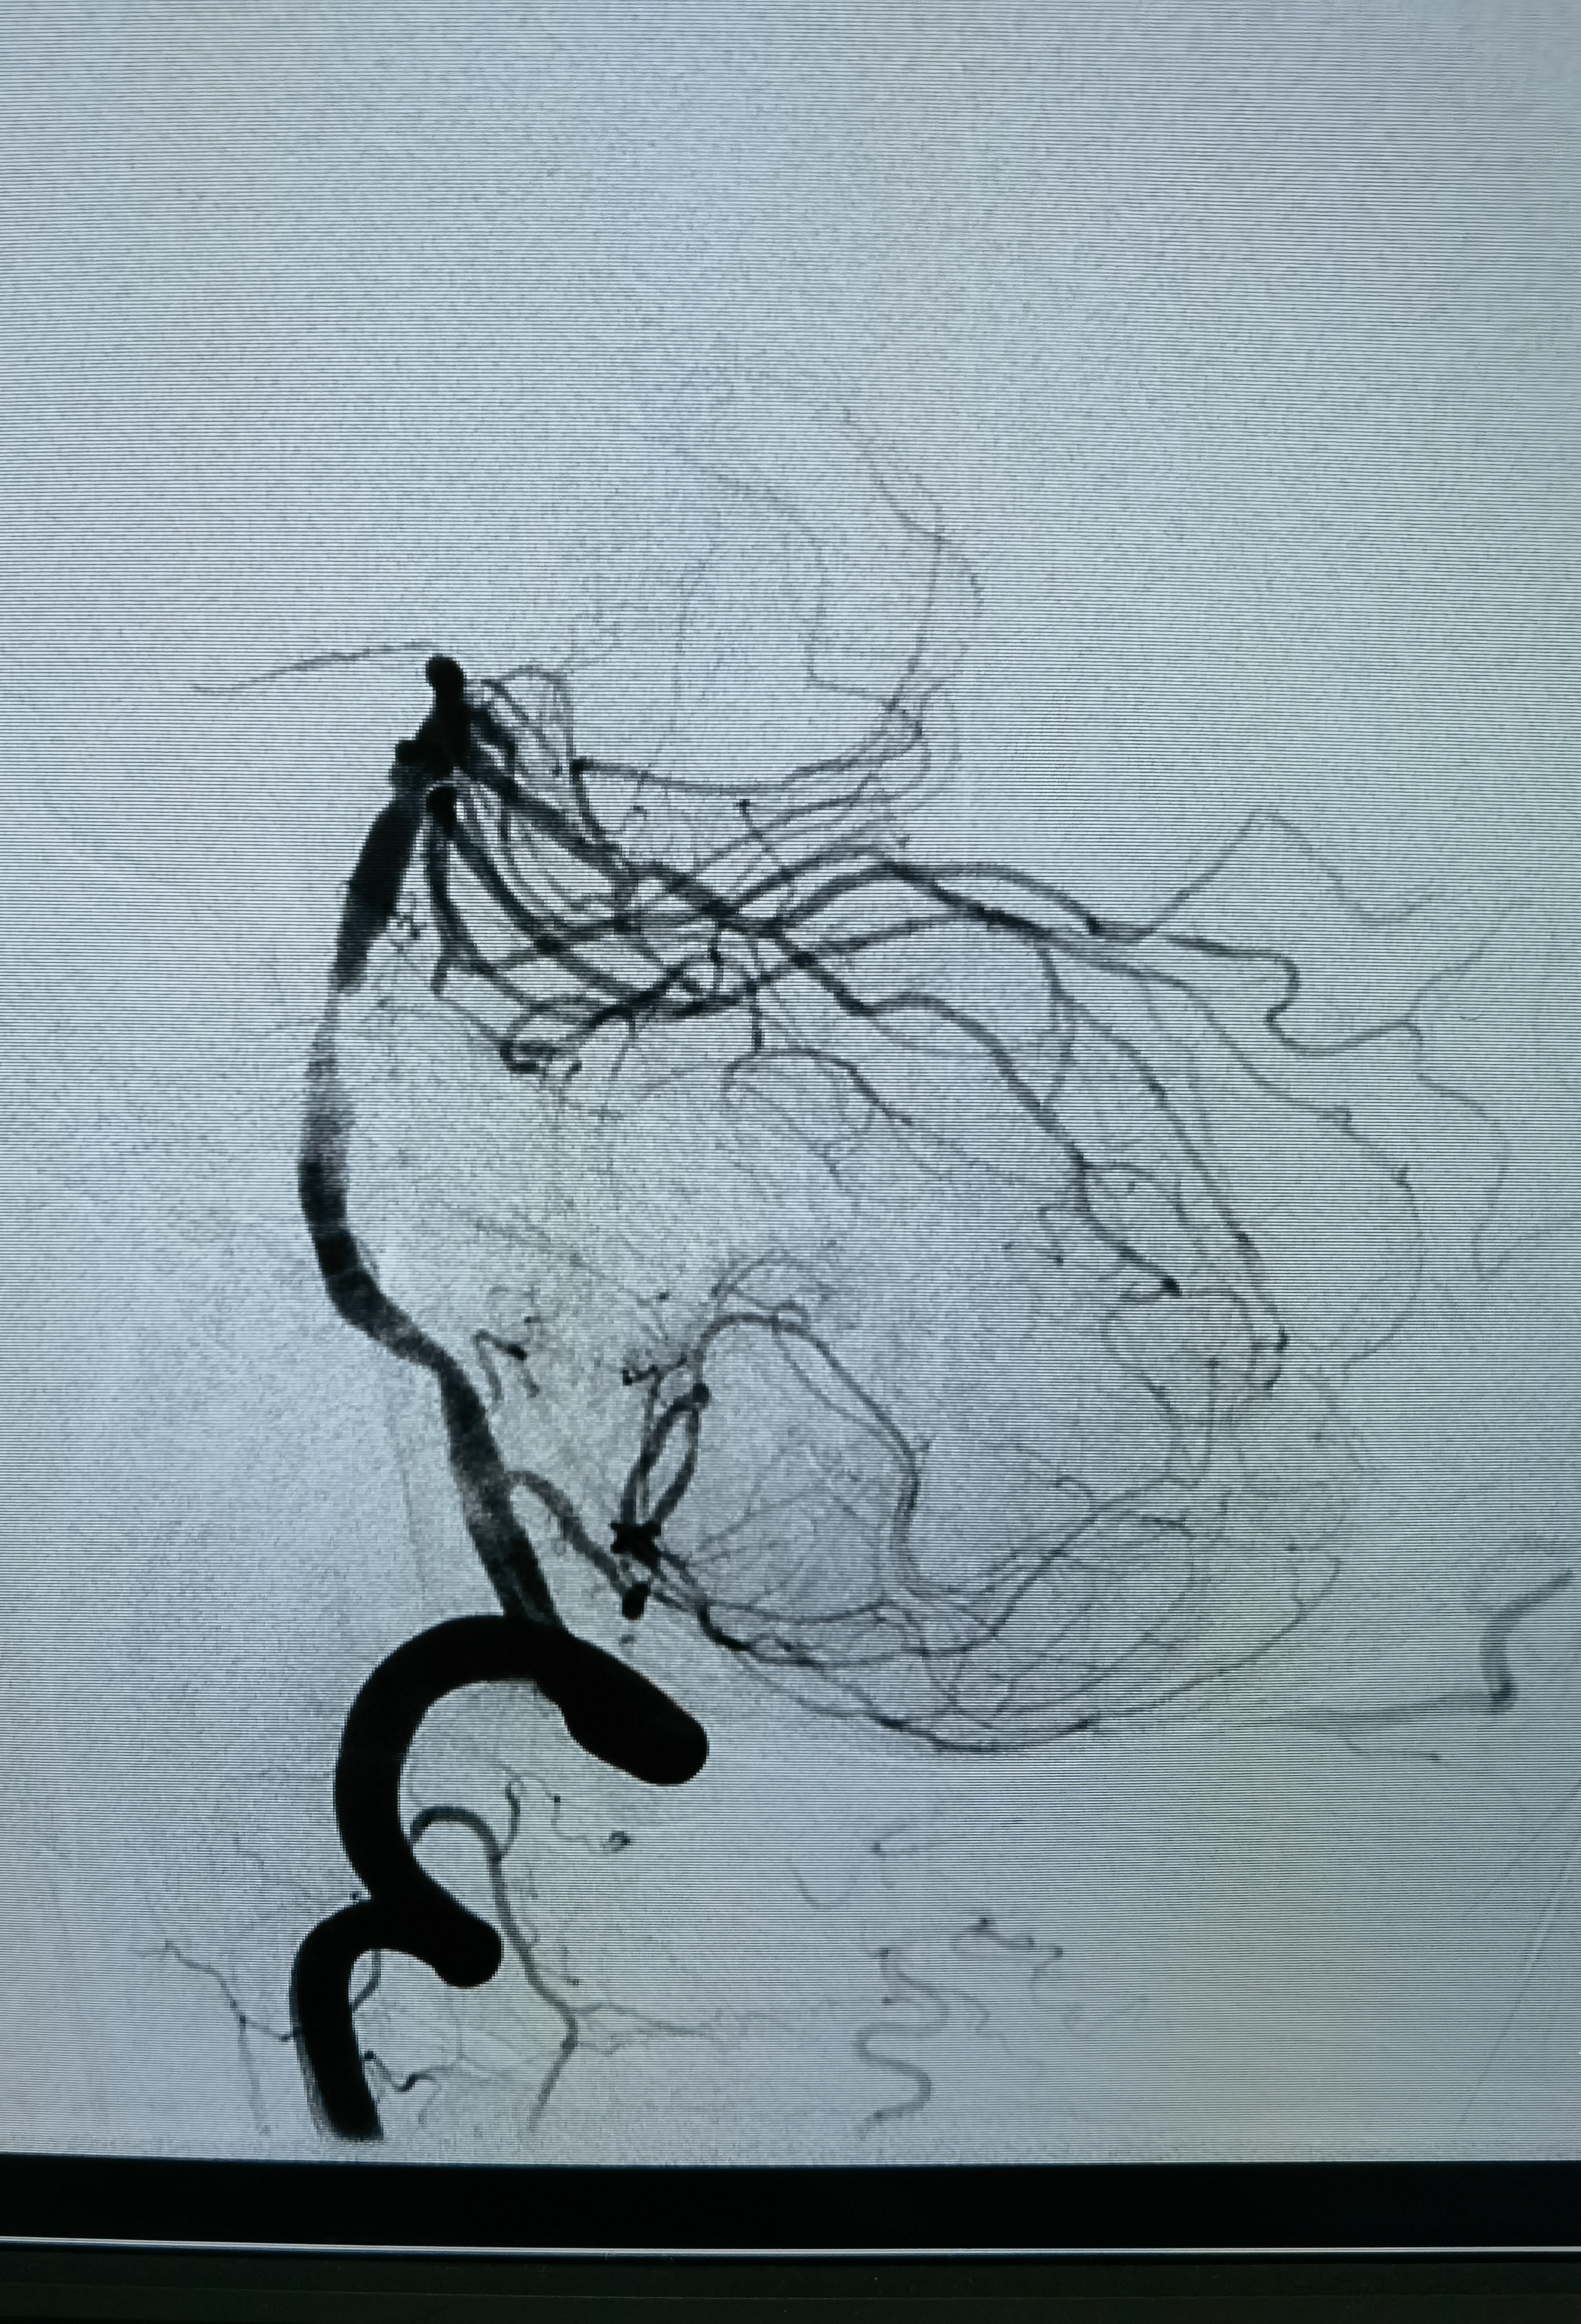

正位造影

侧位造影

工作位造影

狭窄85%